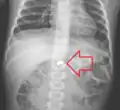

A coin seen on lateral CXR in the esophagus -